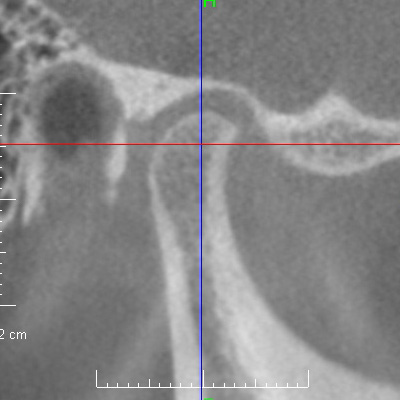

治療前

[6歳4か月]

一見普通に見えますが、患者さんは無意識に(上下の歯がしっかり当たる位置まで)下顎を前に出して咬む習慣がありました。【顎関節CBCT画像】下顎頭は顎関節窩から大きく前にずれています(ポスチャリングといいます)。

今後の成長に深く関わるため、顎関節を含めて詳細な検査・診断が不可欠です。特に顎関節はMRIで円板転位の状態を把握する必要があります。成長加速期には、下顎の成長を最大限に引き出したいと考えます。

R

L